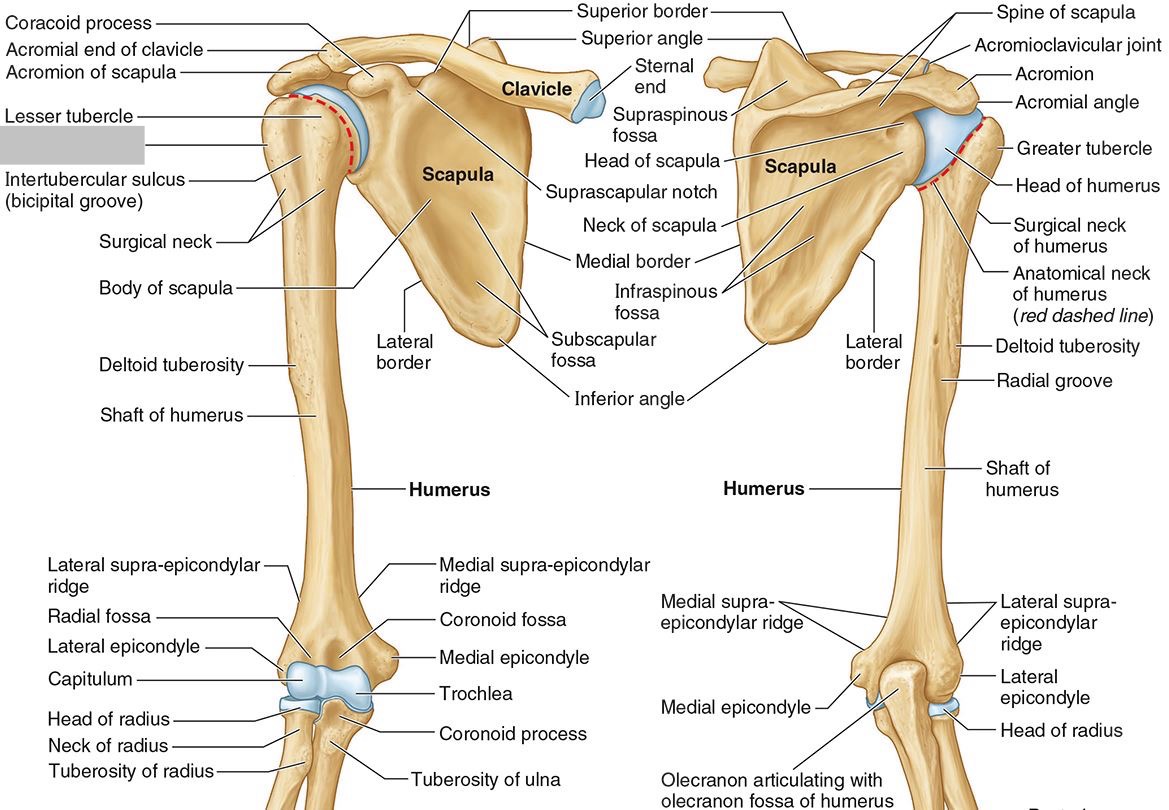

What part of the humerus is this?

The head of the humerus articulates with the scapula at the glenohumeral joint.

What part of the humerus is this?

The anatomic neck is an indentation distal to the head and provides an attachment for the fibrous joint capsule of the glenohumeral joint.

What part of the humerus is this?

The greater tubercle lies lateral and distal to the anatomic neck.

What part of the humerus is this?

The lesser tubercle lies on the anterior/medial side of the humerus, just distal the anatomic neck.

What part of the humerus is this?

The intertubercular (bicipital) groove lies between the greater and lesser tubercles.

What part of the humerus is this?

The surgical neck is a narrow area distal to the tubercles. It is a common site for proximal humerus fractures.

What part of the humerus is this?

The humeral shaft features the deltoid tuberosity laterally for the distal insertion of the deltoid muscle.

What part of the humerus is this?

The radial groove is an oblique depression that contains the radial nerve and deep brachial artery.

Which parts of the humerus is this?

The medial and lateral epicondyles are distal prominences to which many forearm tendons attach, near the elbow joint.

Which parts of the humerus is this?

The medial and lateral supracondylar ridges extend superiorly from the medial and lateral epicondyles.

Which parts of the humerus is this?

The trochlea and the capitulum (the condyles) are the most distal surfaces of the humerus, where it articulates with the forearm bones at the elbow joint

What part of the humerus is this?

The olecranon fossa is a posterior depression above the trochlea that receives that olecranon process of the ulna

What part of the humerus is this?

The coronoid fossa is an anterior depression above the trochlea that receives that coronoid process of the ulna.